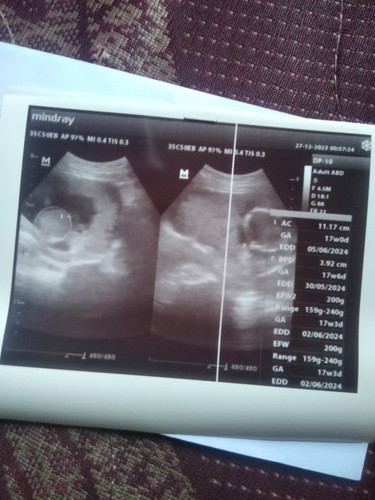

Alhamdulillah USG pertama semua sehat usia kehamilan 17w3dππ